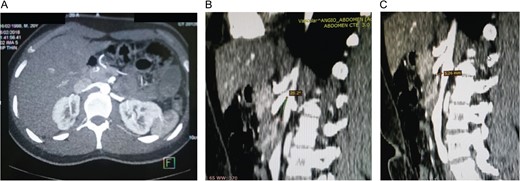

At the time of the assessment in the emergency room, clinical examination revealed dehydration, and abdominal examination revealed periumbilical pain without any tenderness or masses. Laboratory exams revealed anemia and stomach distention was noted on abdominal x-ray. An upper endoscopy was performed revealing a tortuous duodenum in its second and third portions and an extrinsic compression that partially limited the pass of the endoscopy at this point. Due to these findings, surgical consultation was required. A contrast-enhanced CT showed a narrowing at the SMA origin without signs of obstruction (Fig. 1A). An angiotomography with a vascular reconstruction (Fig. 2A) later revealed a 20.5° aortomesenteric angle (Fig. 1B) and 5.26 mm of aortomesenteric distance (Fig. 1C).

(A) Narrowing at the level of the origin of the superior mesenteric artery without signs of obstruction. (B) Vascular reconstruction showing a 20.5° aortomesenteric angle. (C) Vascular reconstruction showing a closed aortomesenteric angle and a short aortomesenteric distance.